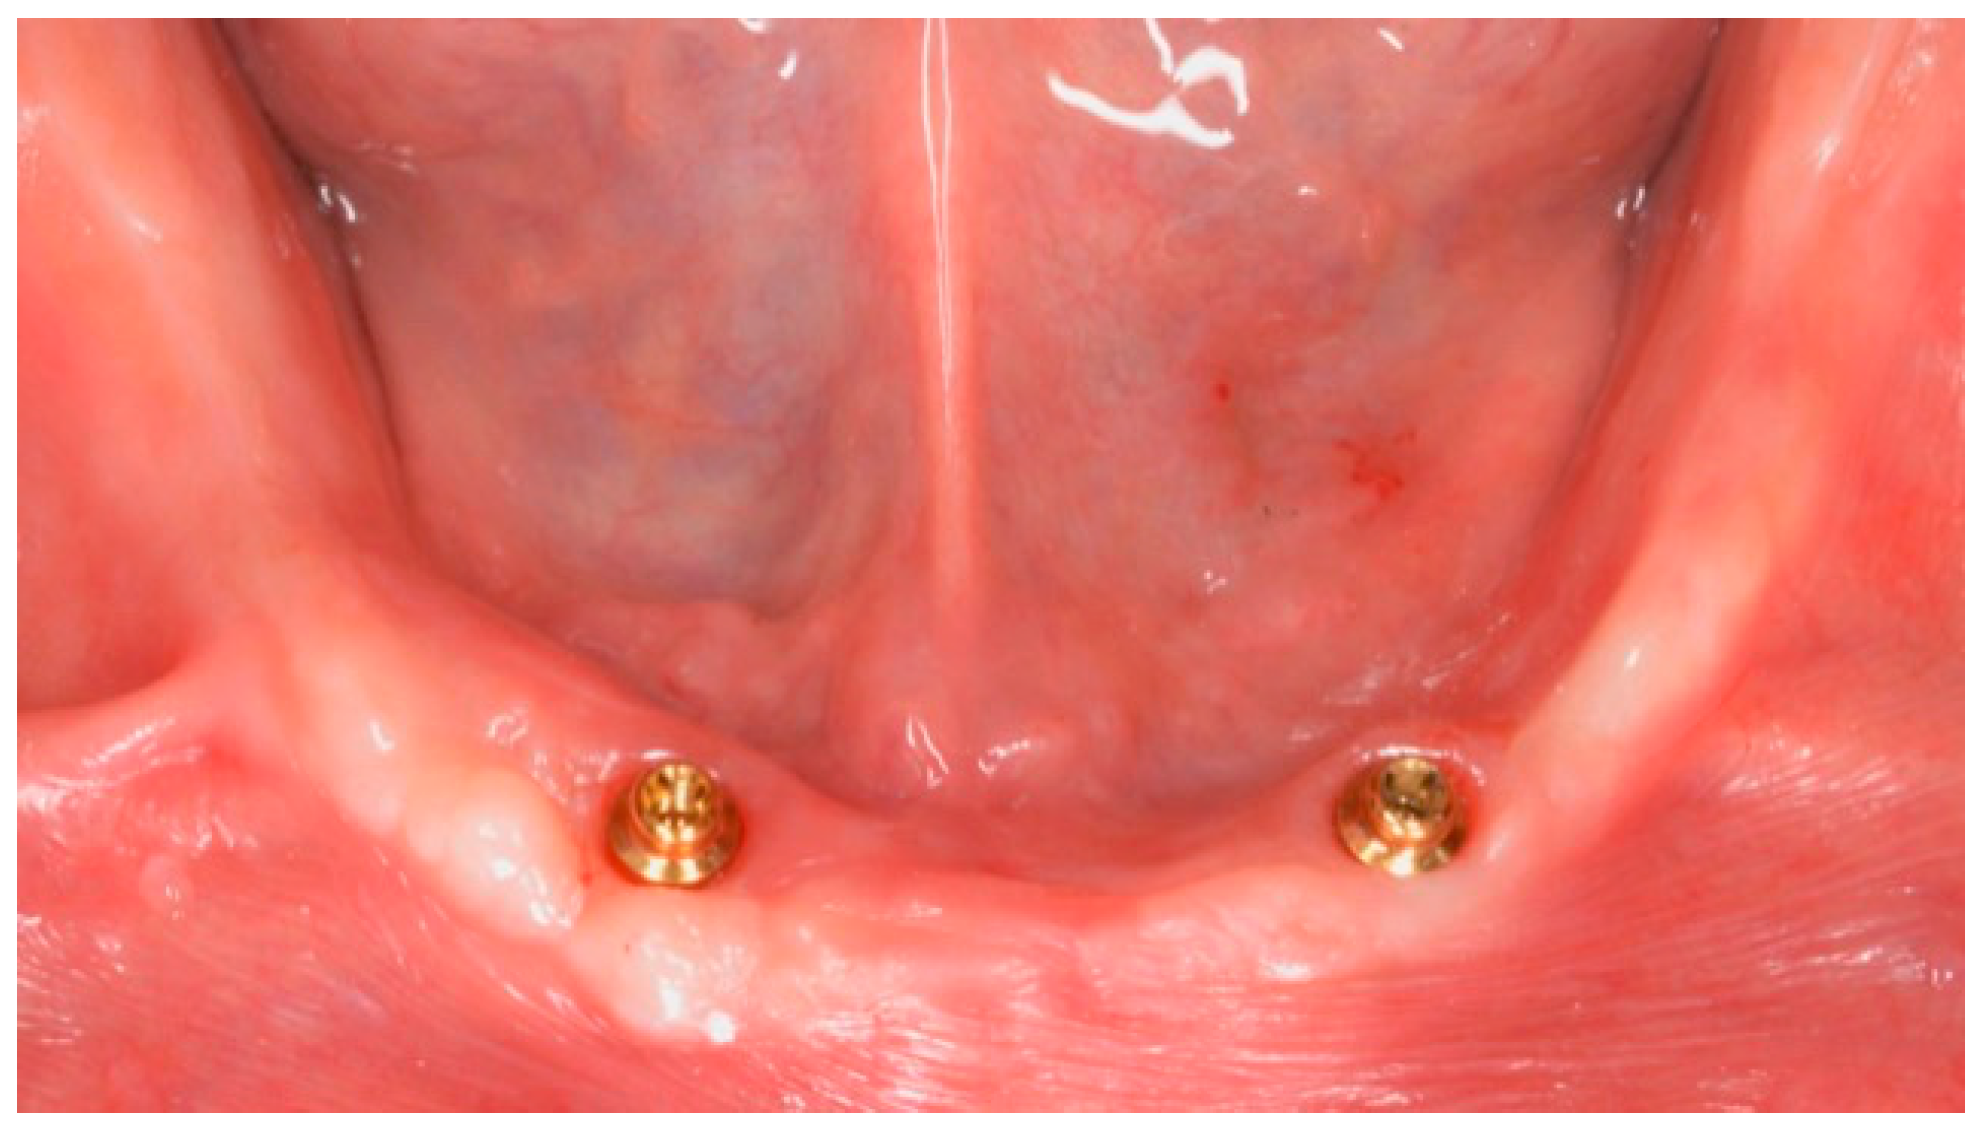

Patients were rehabilitated with both implant-retained or -supported overdentures. In case of implant-retained overdentures, pre-existing or a new developed complete removable dentures were used followed standardized techniques [25]. Implant-retained overdentures were delivered on 1 to 5 unsplinted implants. The following attachment systems were used: Equator attachments (OT Equator, Rhein83, Bologna, Italy), ball attachments (OT Cap, Rhein83), or Locator attachments (Zest Dental Solutions, Carlsbad, CA, USA) (Figure 1, Figure 2, Figure 3 and Figure 4). The Rhein83 OT Equator is a low profile castable and direct implant overdenture attachments with a low vertical profile of 2.1 mm and diameter of 4.4 mm. This system offers multiple solutions for overdenture treatment planning when vertical space limitations are a consideration.

Figure 1. Mandibular overdenture bar with balls attachments.